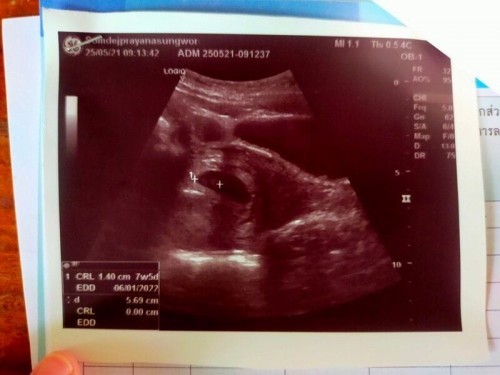

คือเมื่อวานไปซาวด์มาค่ะได้ 7w5d หมอบอกว่าเจอน้องแล้วแต่ยังไม่เจอหัวใจน้องค่ะ แล้วตัวของเราก็มีพาหะธาลัสซีเมีย แต่หมอบอกว่าแฟนแข็งแรงลูกอาจจะไม่เป็นก็ได้ หมอเลยบอกจะส่งตัวเราไปที่รพ.ในเมือง เพื่อไปเจาะเลือดใหม่ค่ะ หมอนัดอีกที 13 กรกฎาคม หรือท้องได้ 14 w ค่ะ ก็เลยกังวลนิดหน่อยกลัวว่าน้องจะไม่อยู่ด้วยค่ะ😖